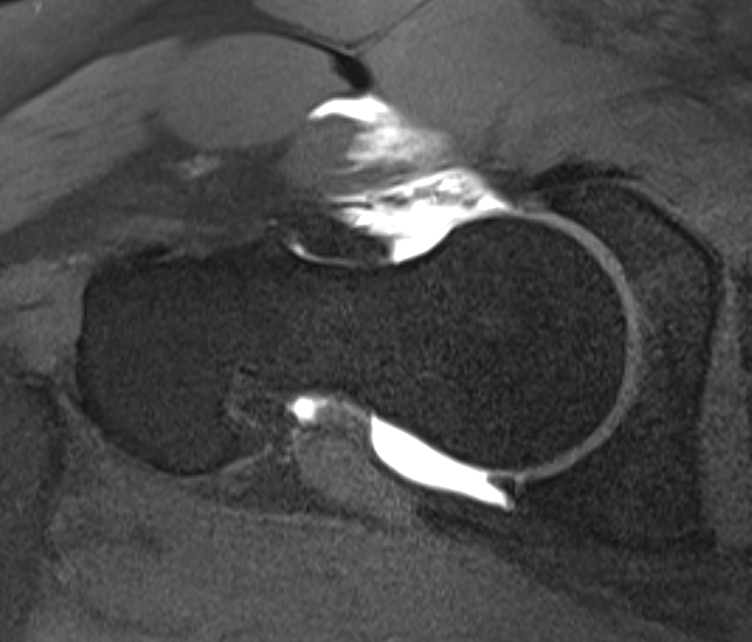

Capsular retear / deficiency

- may cause microinstability / pain

- most studies point towards superior outcomes with capsular repair

Anterior capsular deficiency on MRA post hip arthroscopy